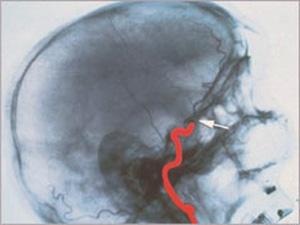

Egy halott agy röntgenképe

Az agyhalál visszafordíthatatlan, tehát azonos az egyén halálával hagyományos, köznapi értelemben véve. Az agy - azaz a nagyagy, kisagy és az agytörzs - működésének teljes és visszafordíthatatlan megszűnése. Az agyfunkciók, mint például a fájdalomérzékelés, a gondolkodás, a légzés irányítása, az anyagcsere-folyamatok szabályozása végérvényesen elvesznek. Ugyanez a helyzet az agy vérellátásával is. S bár a testet - a szervezet alapfunkcióit, és a transzplantálható szerveket - gépekkel még életben lehet tartani, de ez esetben - ellentétben a kómával - teljességgel kizárható, hogy az agy irányító funkciói és az eszmélet valaha is visszatérnek.